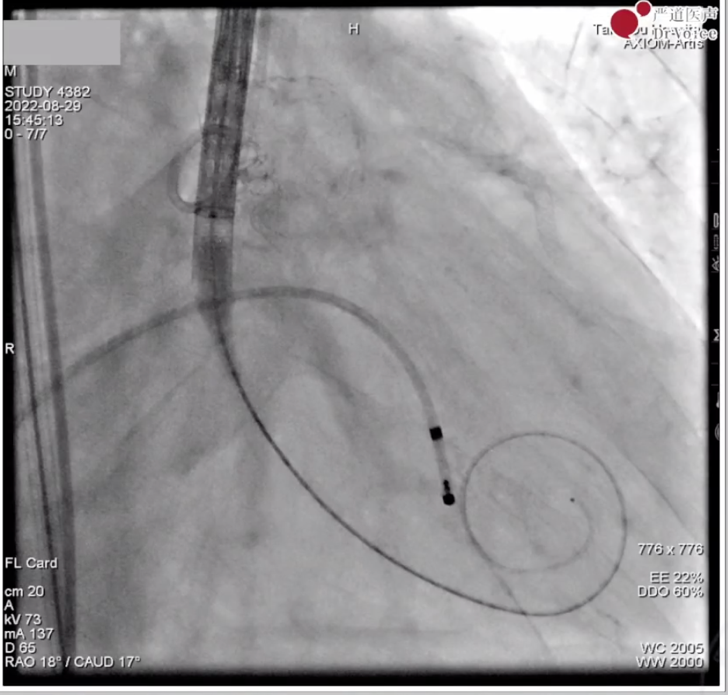

瓣膜最终形态及造影显示位置和形态良好。

即刻食道超声见瓣架展开充分,微量瓣周漏,平均跨瓣压差7mmHg。